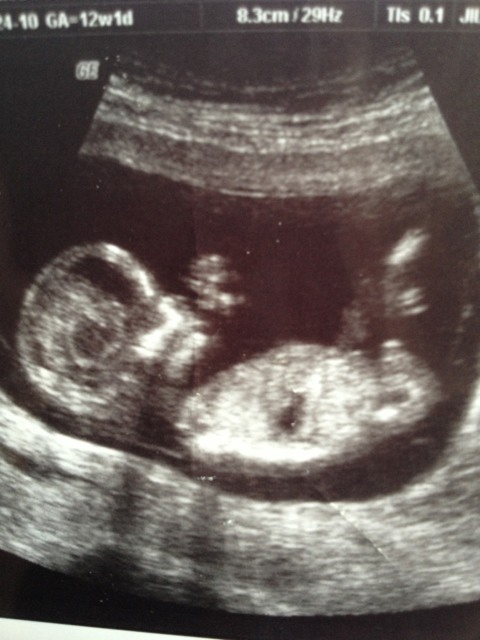

U/S tech didn't really know about the nub shot so she did a potty shot instead. It seems very very much like it is a boy from the pic. Are potty shots accurate that early? I swayed for a girl and already have two lovely boys. Tech was convinced it was a boy too. Attachment 10387Attachment 10388